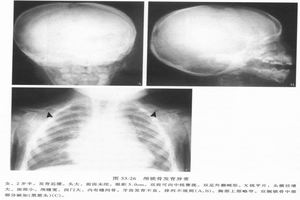

1.X線檢查MAS的骨組織被異常增生的纖維組織所取代,表現為不同程度的骨膨脹,骨皮質變薄,但完整。骨密度可為均勻性減低,或呈磨玻璃樣,或見條索狀、斑點緻密陰影。國內總結X線分4型:

(1)囊狀改變:分單囊和多囊,邊緣硬化,囊內常見條狀骨及斑點狀緻密影,常見於管狀骨和肋骨。

(2)毛玻璃改變:髓腔囊狀膨脹呈毛玻璃狀密度,內可有條狀骨紋和斑點狀鈣化。

(3)絲瓜筋狀改變:骨小梁粗大扭曲,頗似絲瓜筋狀,嚴重者如蛛網狀,長管狀骨粗大,骨狀紋一般和縱軸平行。

(4)蟲蝕狀改變:單發或多發的溶骨性改變,邊緣銳利如蟲蝕樣,可類似溶骨性轉移性破壞。

此外,脊柱和長骨常伴病理性骨折。